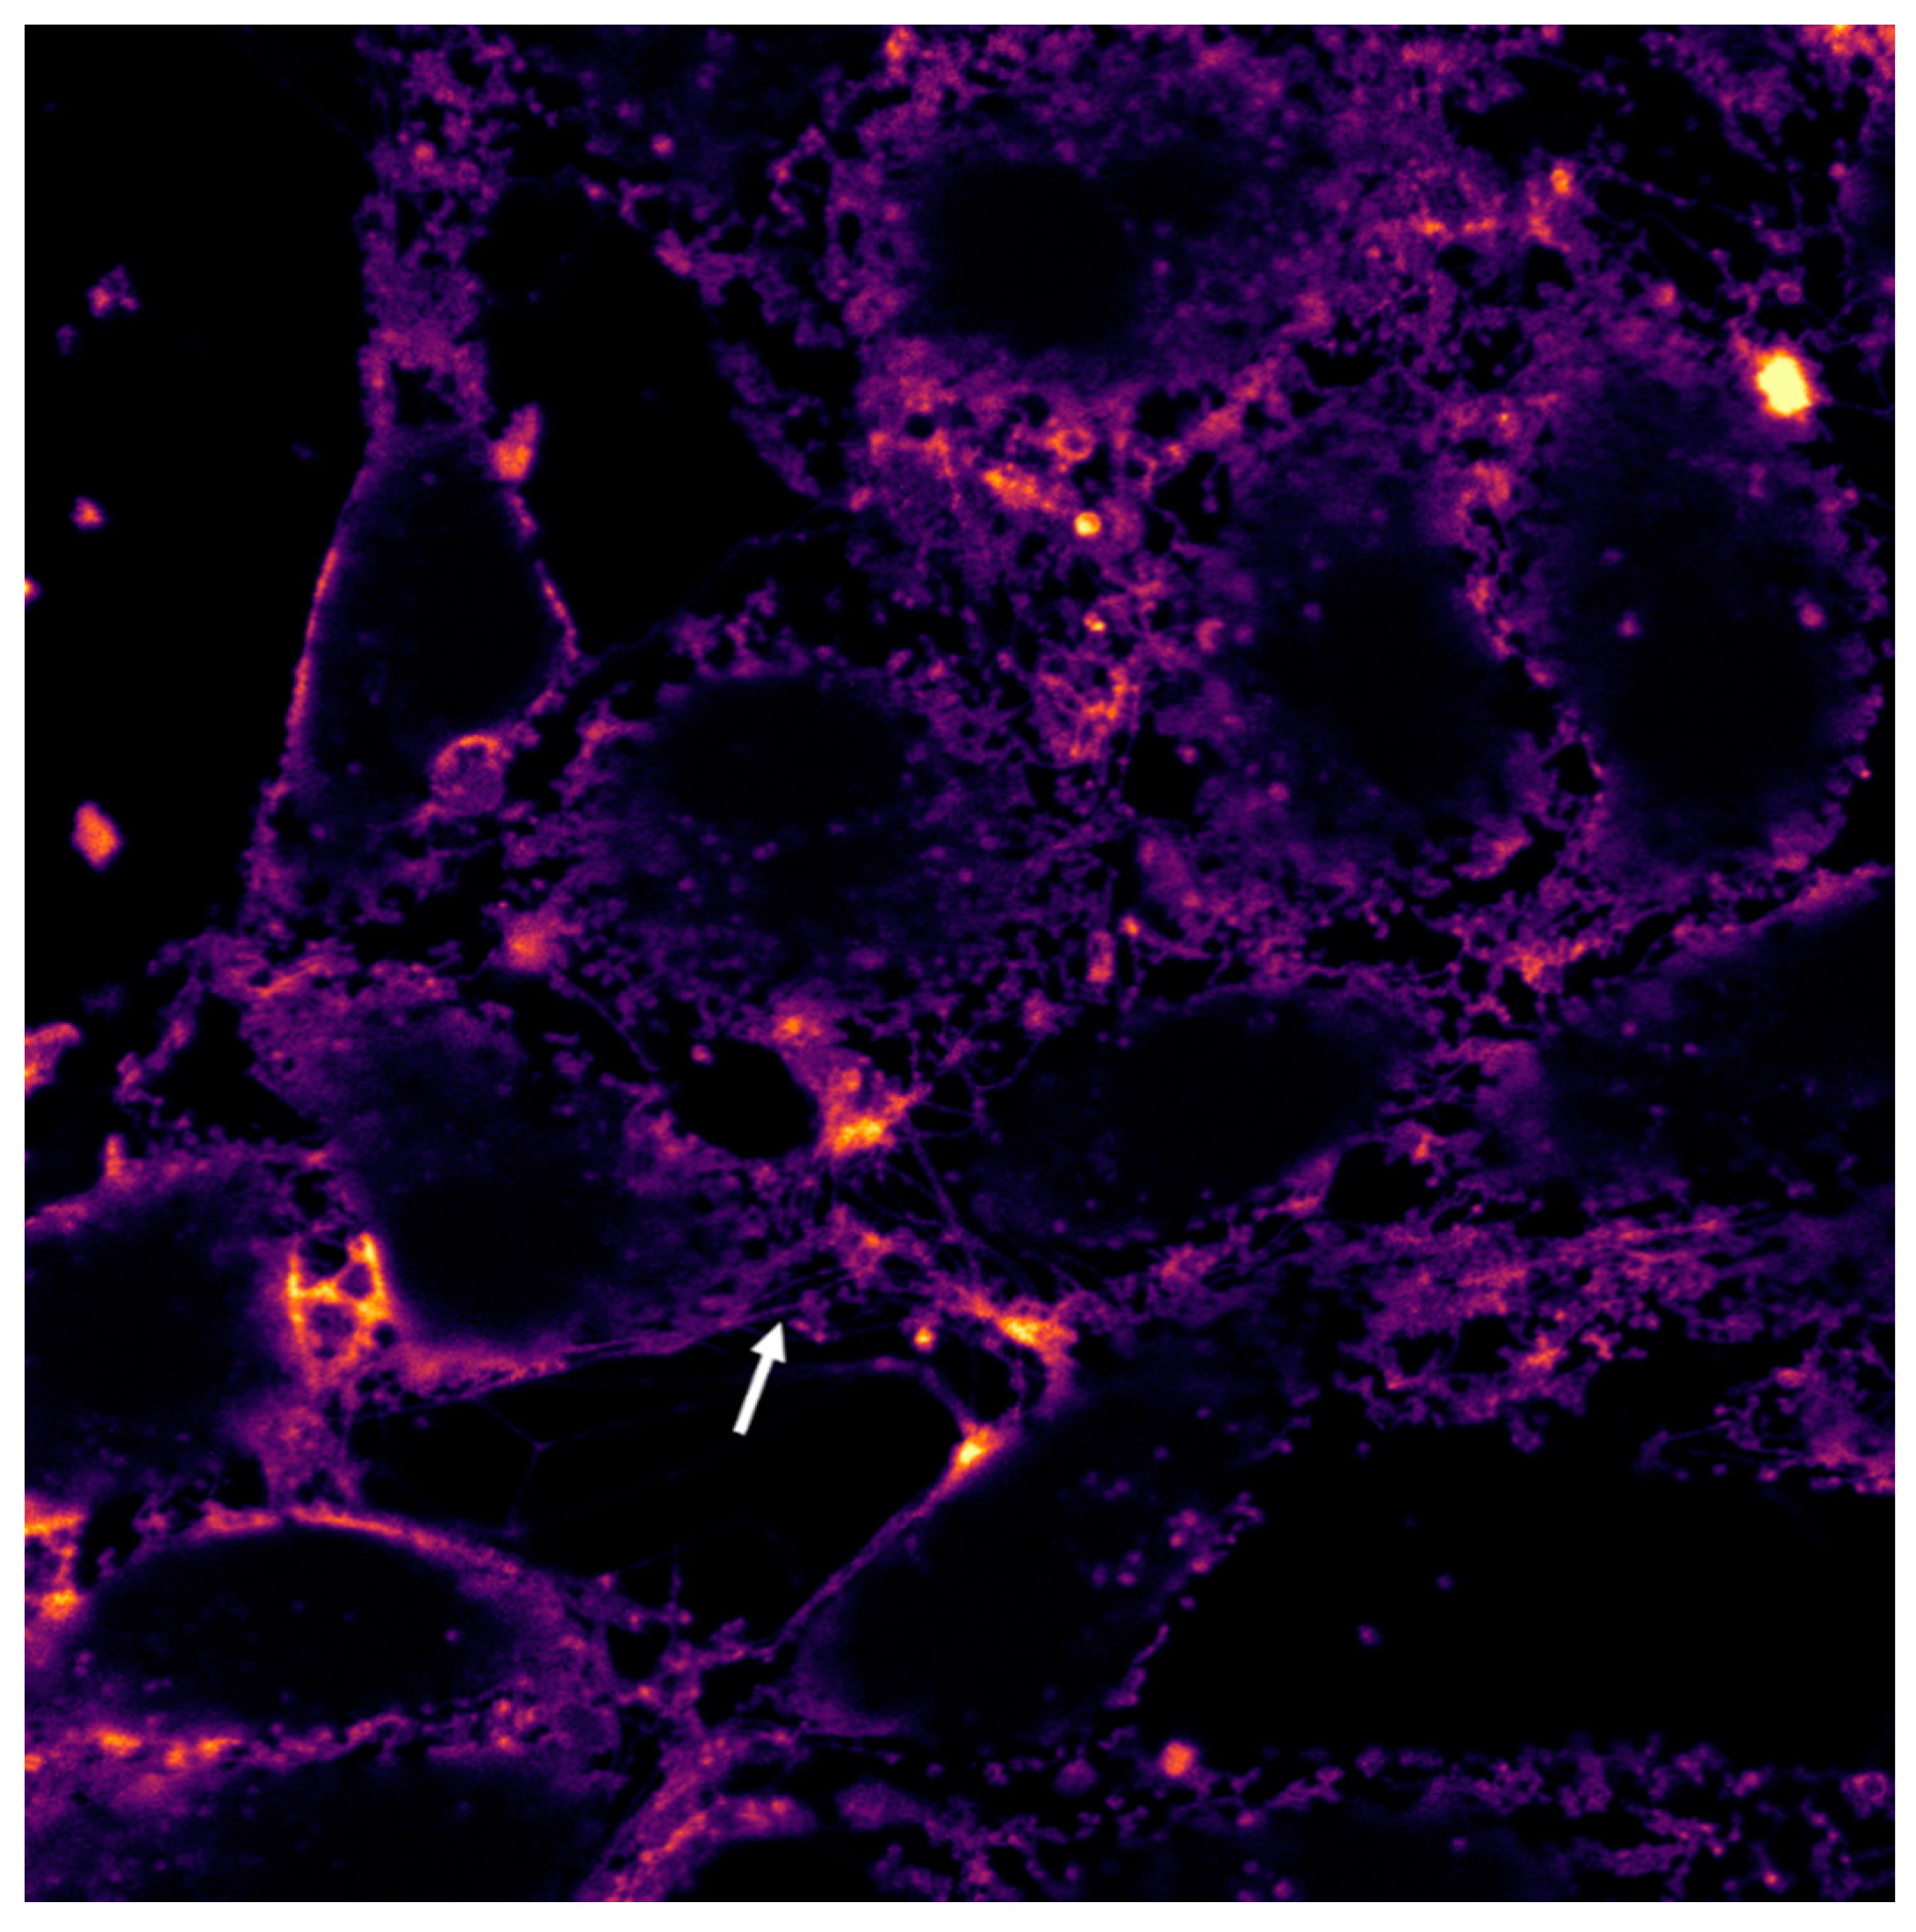

2.7. Vero Cell Culture Tests

3.2.3. Cell and Tissue Staining

3.2.4. Microscopic Examination